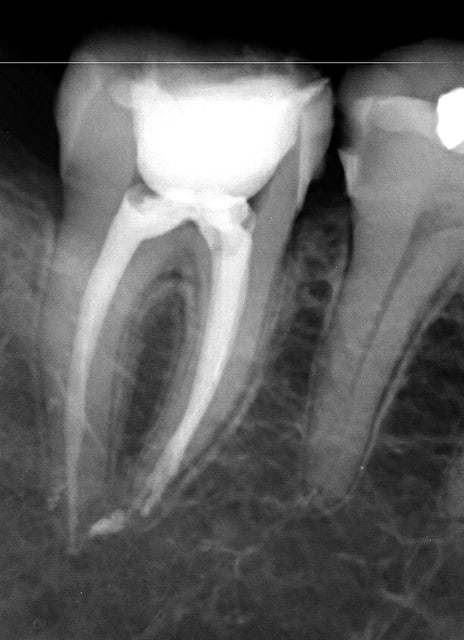

Endo de ce matin :

--

www.dentaltradegroup.com

Endo 3  2  c nes txljrd - Eugenol

Endo 3  3  fin a4y8gs - Eugenol